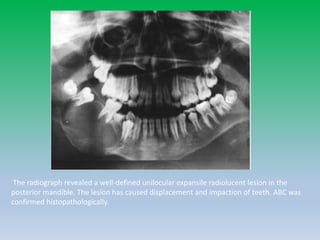

The radiograph revealed a well-defined unilocular expansile radiolucent lesion in the

posterior mandible. The lesion has caused displacement and impaction of teeth. ABC was

confirmed histopathologically.